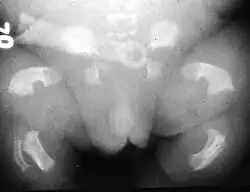

O nanismo tanatofórico ou displasia tanatofórica é uma displasia esquelética do grupo heterogéneo das desordens associadas ao crescimento ósseo, com uma interferência muito significativa no seu tamanho, forma e densidade. Foi muitas vezes confundida com a acondroplasia, no entanto, corresponde a uma manifestação mais severa e letal, que se distingue por micromelia (encurtamento dos membros) grave e que habitualmente resulta na morte do feto in útero ou pouco tempo após o nascimento. Através de conhecimentos e técnicas actuais, alguns casos clínicos do passado viram o diagnóstico alterado de acondroplasia para nanismo tanatofórico.[1][2][3][4][5][6]

Esta patologia provoca uma disrupção generalizada das placas de crescimento com persistência de tecido mesenquimal [4]. As evidências são de uma osteocondroplasia letal, caracterizada por rizomelia (encurtamento das porções proximais), micromelia (extremo encurtamento dos membros), cabeça desproporcionalmente grande com uma área de depressão na porção medial da face, deformações cranianas normalmente provocadas por craniostenose (encerramento prematuro das suturas), esqueleto axial longo comparativamente com o esqueleto apendicular e hipoplasia torácica (redução acentuada do tórax).[7][2][3][4][9]

O Tipo 1 caracteriza-se por rizomelia extrema. A nível craniano, a base do occipital apresenta uma dimensão reduzida, incluindo o foramen magnum, testa proeminente e hipertelorismo ocular (afastamento amplificado das cavidades orbitais). No tórax ocorre platispondilia vertebral (achatamento dos corpos vertebrais) e as costelas apresentam encurtamento com extremidades metafisárias em forma de “chávena”, características que lhe conferem uma configuração mais estreita e em forma de triângulo. Na cintura pélvica, o ílion apresenta uma dimensão mais curta com a margem inferior horizontal, e o ísquion e a púbis possuem uma fisionomia mais larga e curta. Os membros superiores e inferiores caracterizam-se por ossos longos arqueados com diminuição muito significativa do comprimento e com metáfises alargadas. O fémur destaca-se pela sua aparência semelhante a um “auscultador de telefone”. Os membros superiores por vezes podem apresentam dígitos encurtados, verificando-se por vezes sinostose rádio-cubital.[4][6]

O Tipo 2 corresponde a uma manifestação menos severa e mais rara. A alteração mais distintiva observa-se a nível craniano, pela sua forma de “folha de trevo” devido à craniossinostose/oxicefalia (encerramento prematuro da sutura coronal). Os ossos longos apresentam encurtamento, mas uma forma retilínea ao invés de arqueada.[2][3][9][10]